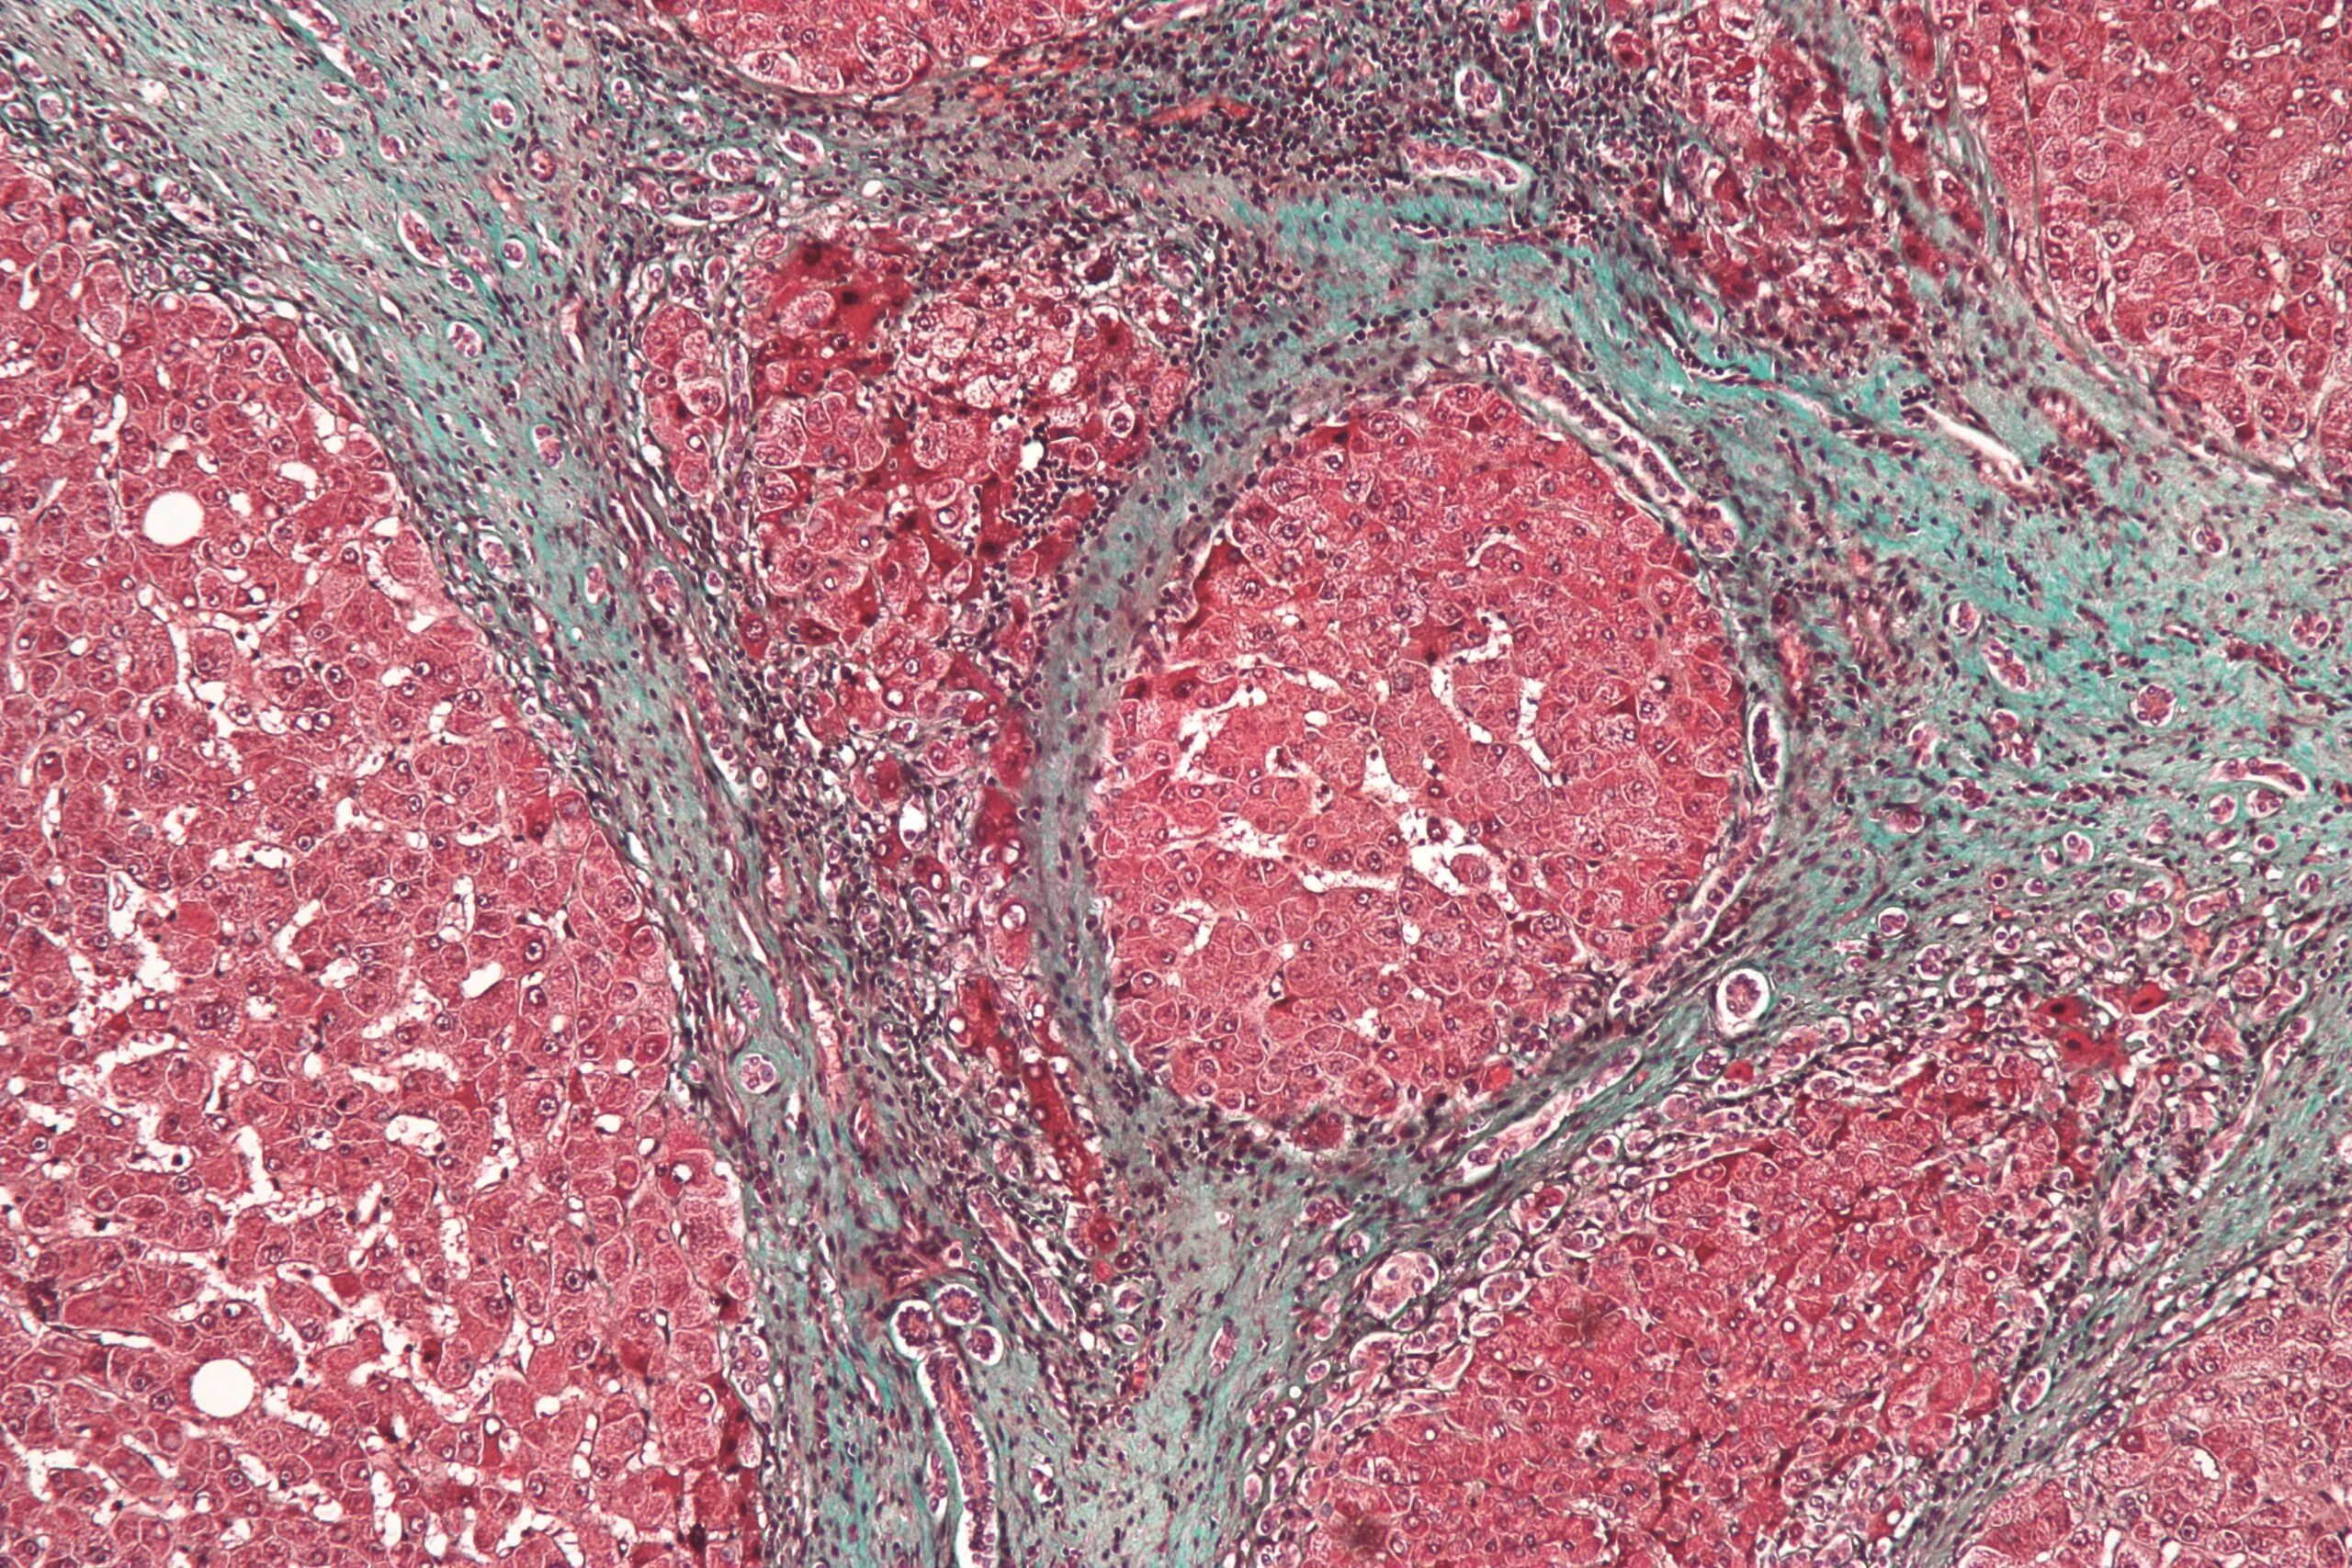

Фиброз 1 степени